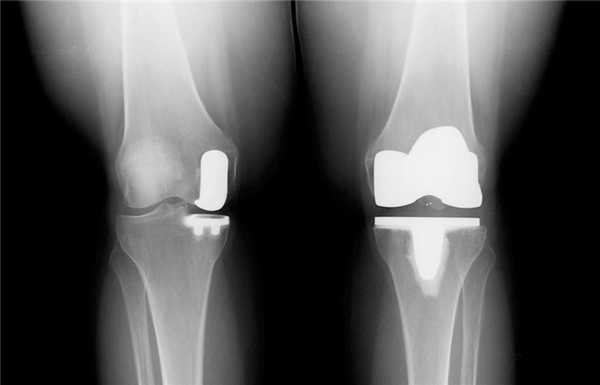

Длительное время ТЭКС (тотальное протезирование коленного сустава) признавался ведущим методом при лечении остеоартроза. Какие же преимущества имеет одномыщелковое эндопротезирование:

- Гораздо меньший объем хирургического вмешательства;

- Быстрый восстановительный период (уже через несколько месяцев пациент может возвращаться к своим повседневным физическим нагрузкам);

- Менее выражен болевой синдром (как в покое, так и при интенсивной физической нагрузке);

- После частичного эндопротезирования люди вдвое реже жалуются на трудности при использовании автомобиля, чем после тотального;

- Вдвое меньше случаев ограничения сгибания в коленном суставе и контрактур;

- Гораздо чаще людям с частичным эндопротезом доступно положение сидя на корточках, посадка и выход из автотранспорта, наклон и подъем предметов с пола, бег.

Целый ряд неоспоримых и важных преимуществ однополюсного протезирования. Большинство зарубежных коллег подчеркивают у себя схожесть приведенных результатов.

Сравнение двух типов операций.